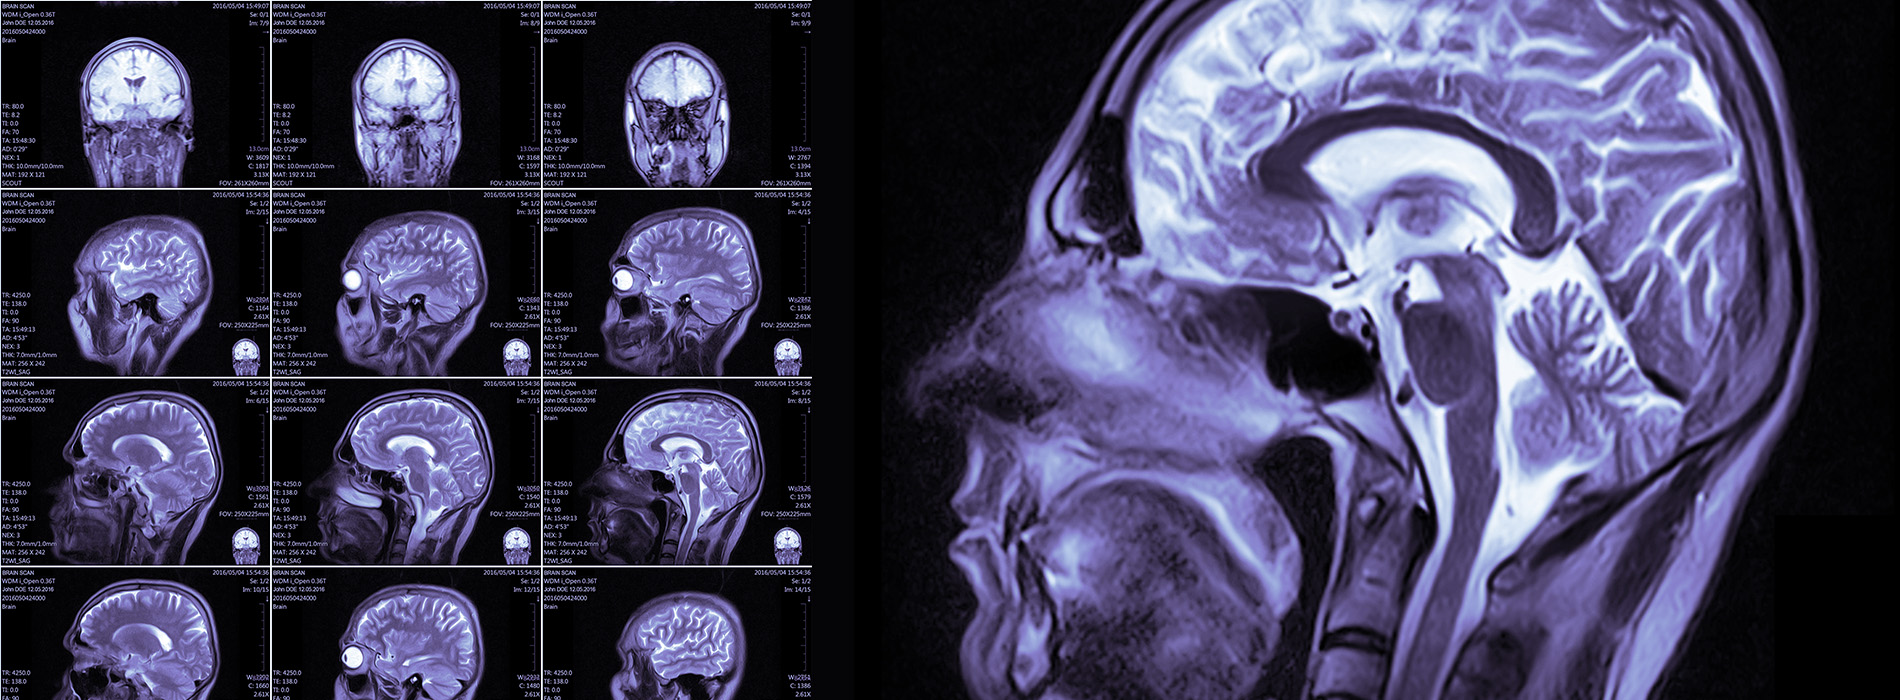

Epilepsy is a prevalent and debilitating neurological condition. Our board-certified specialists in Epilepsy and Neurology are committed to providing top-notch care for patients with refractory epilepsy.

With exceptional fellowship training in epilepsy, extensive experience in treating the condition, and expertise in advanced management options, our team stands out in the field of epilepsy care.

As a state-of-the-art neurology practice, we offer comprehensive services to diagnose, manage, and treat a broad range of neurological conditions in adults and children. Our board-certified professional team provides skilled care and partners with multi-disciplinary medical experts to help patients chart a path to improved health and wellness.